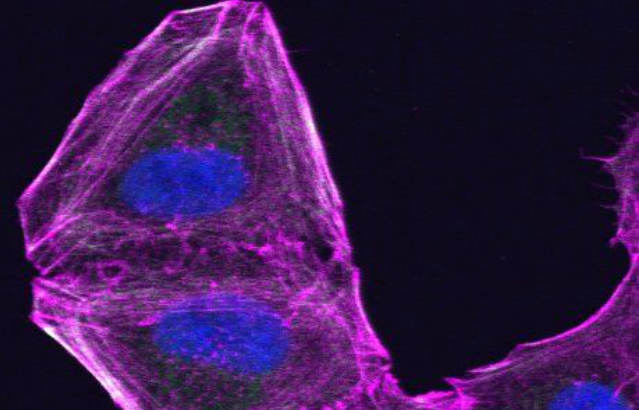

A drug resistant melanoma cell that has altered its cytoskeleton

The team from Barts Cancer Institute found that melanoma cells stop responding to both immunotherapies and drugs targeted at the tumour’s faulty genes by increasing the activity of two cytoskeletal proteins – ROCK and Myosin II. The researchers found that these molecules are key for cancer cell survival and resistance to these treatments.

The molecules had previously been linked to the process of metastatic spread but not to the poor impact of current anti-melanoma therapies. This work points to a strong connection between metastasis and therapy resistance – confirming that the cytoskeleton is important in determining how aggressive a cancer is.